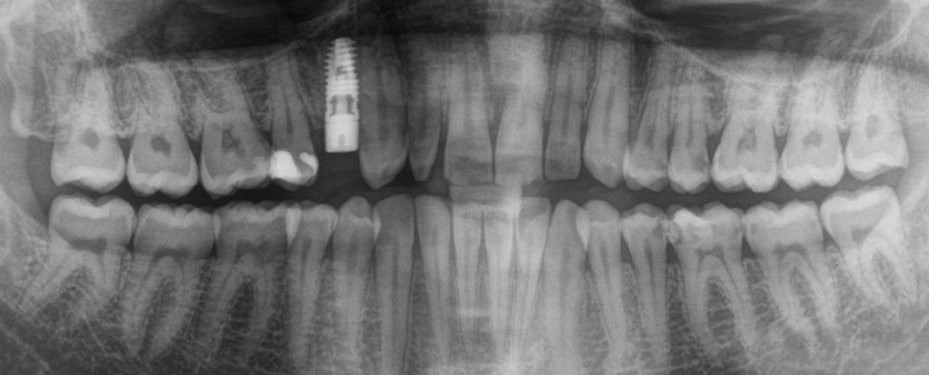

Заканчиваем нашу операцию наложением швов

И контрольным снимком